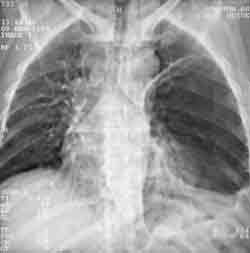

Рис. 1. КТ-топограмма. Левое легкое поджато гигантской буллой, симулирующей спонтанный пневмоторакс. Отмечается смещение средостения вправо.